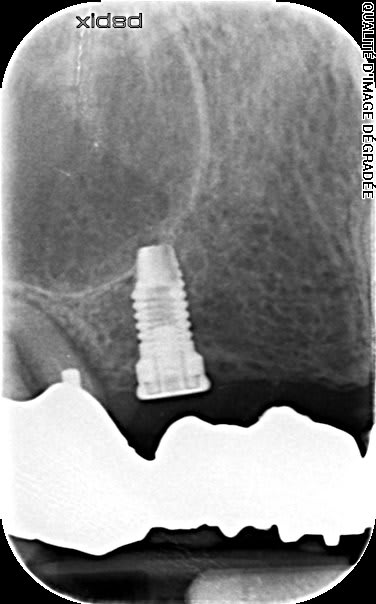

Après accès à l'implant j'ai pris un cliché de la tête qui semble être un hexagone interne.

c'est un hex externe, donc normalement compatible avec tous les accastillages pour hex externe 4.1mm...;-)